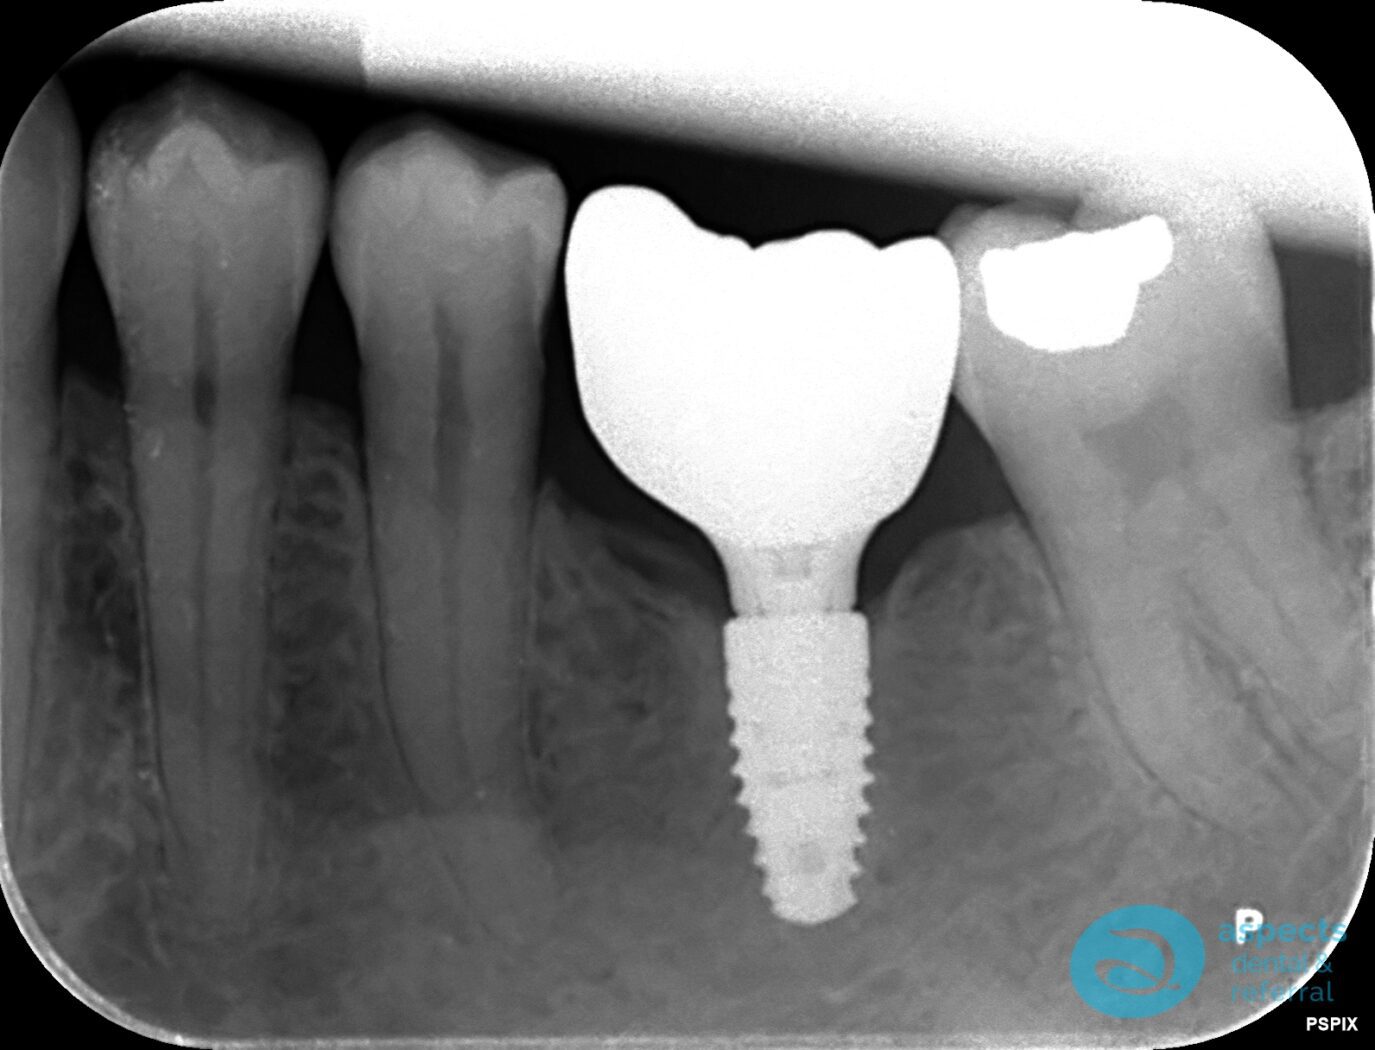

After a 12-week healing period, a Dental Implant was successfully placed at the extraction site. Following adequate osseointegration and soft tissue healing, the implant was restored with an all-ceramic zirconia crown, achieving both functional stability and aesthetic restoration.

After Dental Implant Xray